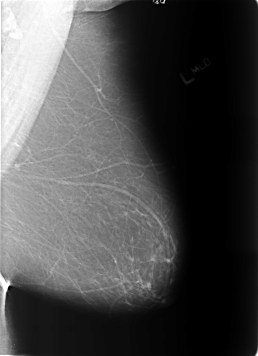

B_3172_1.LEFT_MLO

LEFT_MLO LINES 5696 PIXELS_PER_LINE 4128 BITS_PER_PIXEL 12 RESOLUTION 50 NON_OVERLAY